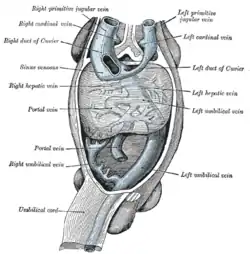

Posterior abdominal wall, after removal of the peritoneum, showing kidneys, suprarenal capsules, and great vessels. (Hepatic veins labeled at center top.) Human embryo with heart and anterior body-wall removed to show the sinus venosus and its tributaries.

Human embryo with heart and anterior body-wall removed to show the sinus venosus and its tributaries. Longitudinal section of a hepatic vein.